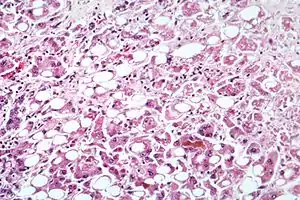

| Alcoholic hepatitis as seen with a microscope, showing fatty changes (white circles), remnants of dead liver cells, and Mallory bodies (twisted-rope shaped inclusions within some liver cells). (H&E stain) | |